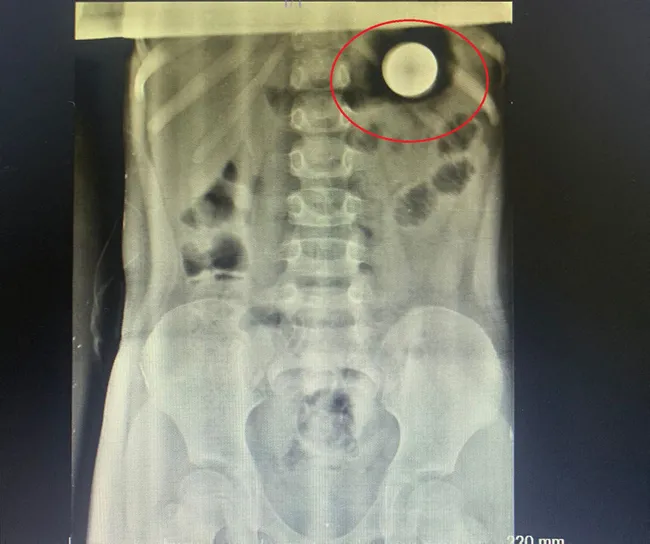

Mersin'de 5 yaşındaki Irmak Pehlivan, madeni 1lira yuttu. 14 gün sonra yaptığı diyetle paradan kurtuldu...

Şaşkına çeviren olay Mersin Tarsus'ta yaandı. Irmak Pehlivan, ailesinin dalgınlıkla ortaya bıraktığı madeni 1 lirayı yuttu. Durumu fark eden ailesi, Irmak'ı hastaneye götürdü. Doktorlar, Irmak'ın parayı doğal yollar ile çıkarmasını beklemesi gerektiğini söyledi. Ancak Irmak, 11 gün boyunca parayı çıkartamadı.

İlçedeki özel bir hastanede görevli Çocuk Sağlığı ve Hastalıkları Uzmanı Dr. Çağlar Altınoluk'un muayene ettiği Irmak'a, özel bir diyet uygulandı. Irmak, diyetin 3 gününde madeni parayı bağırsaklarından atmayı başardı. Irmak, daha sonra doktoru ile fotoğraf çektirdi.